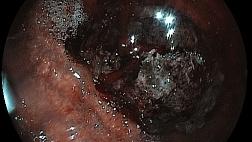

- Атлас